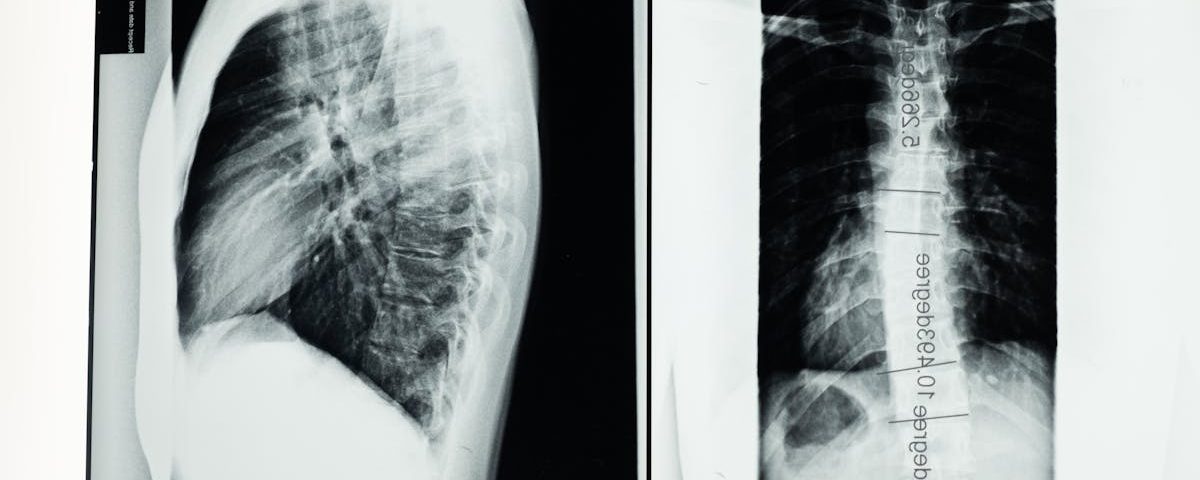

Quels examens sont nécessaires avant de commencer un traitement de décompression pour une protrusion discale?

Une IRM ou une radiographie est généralement recommandée pour évaluer l’état de la colonne vertébrale.